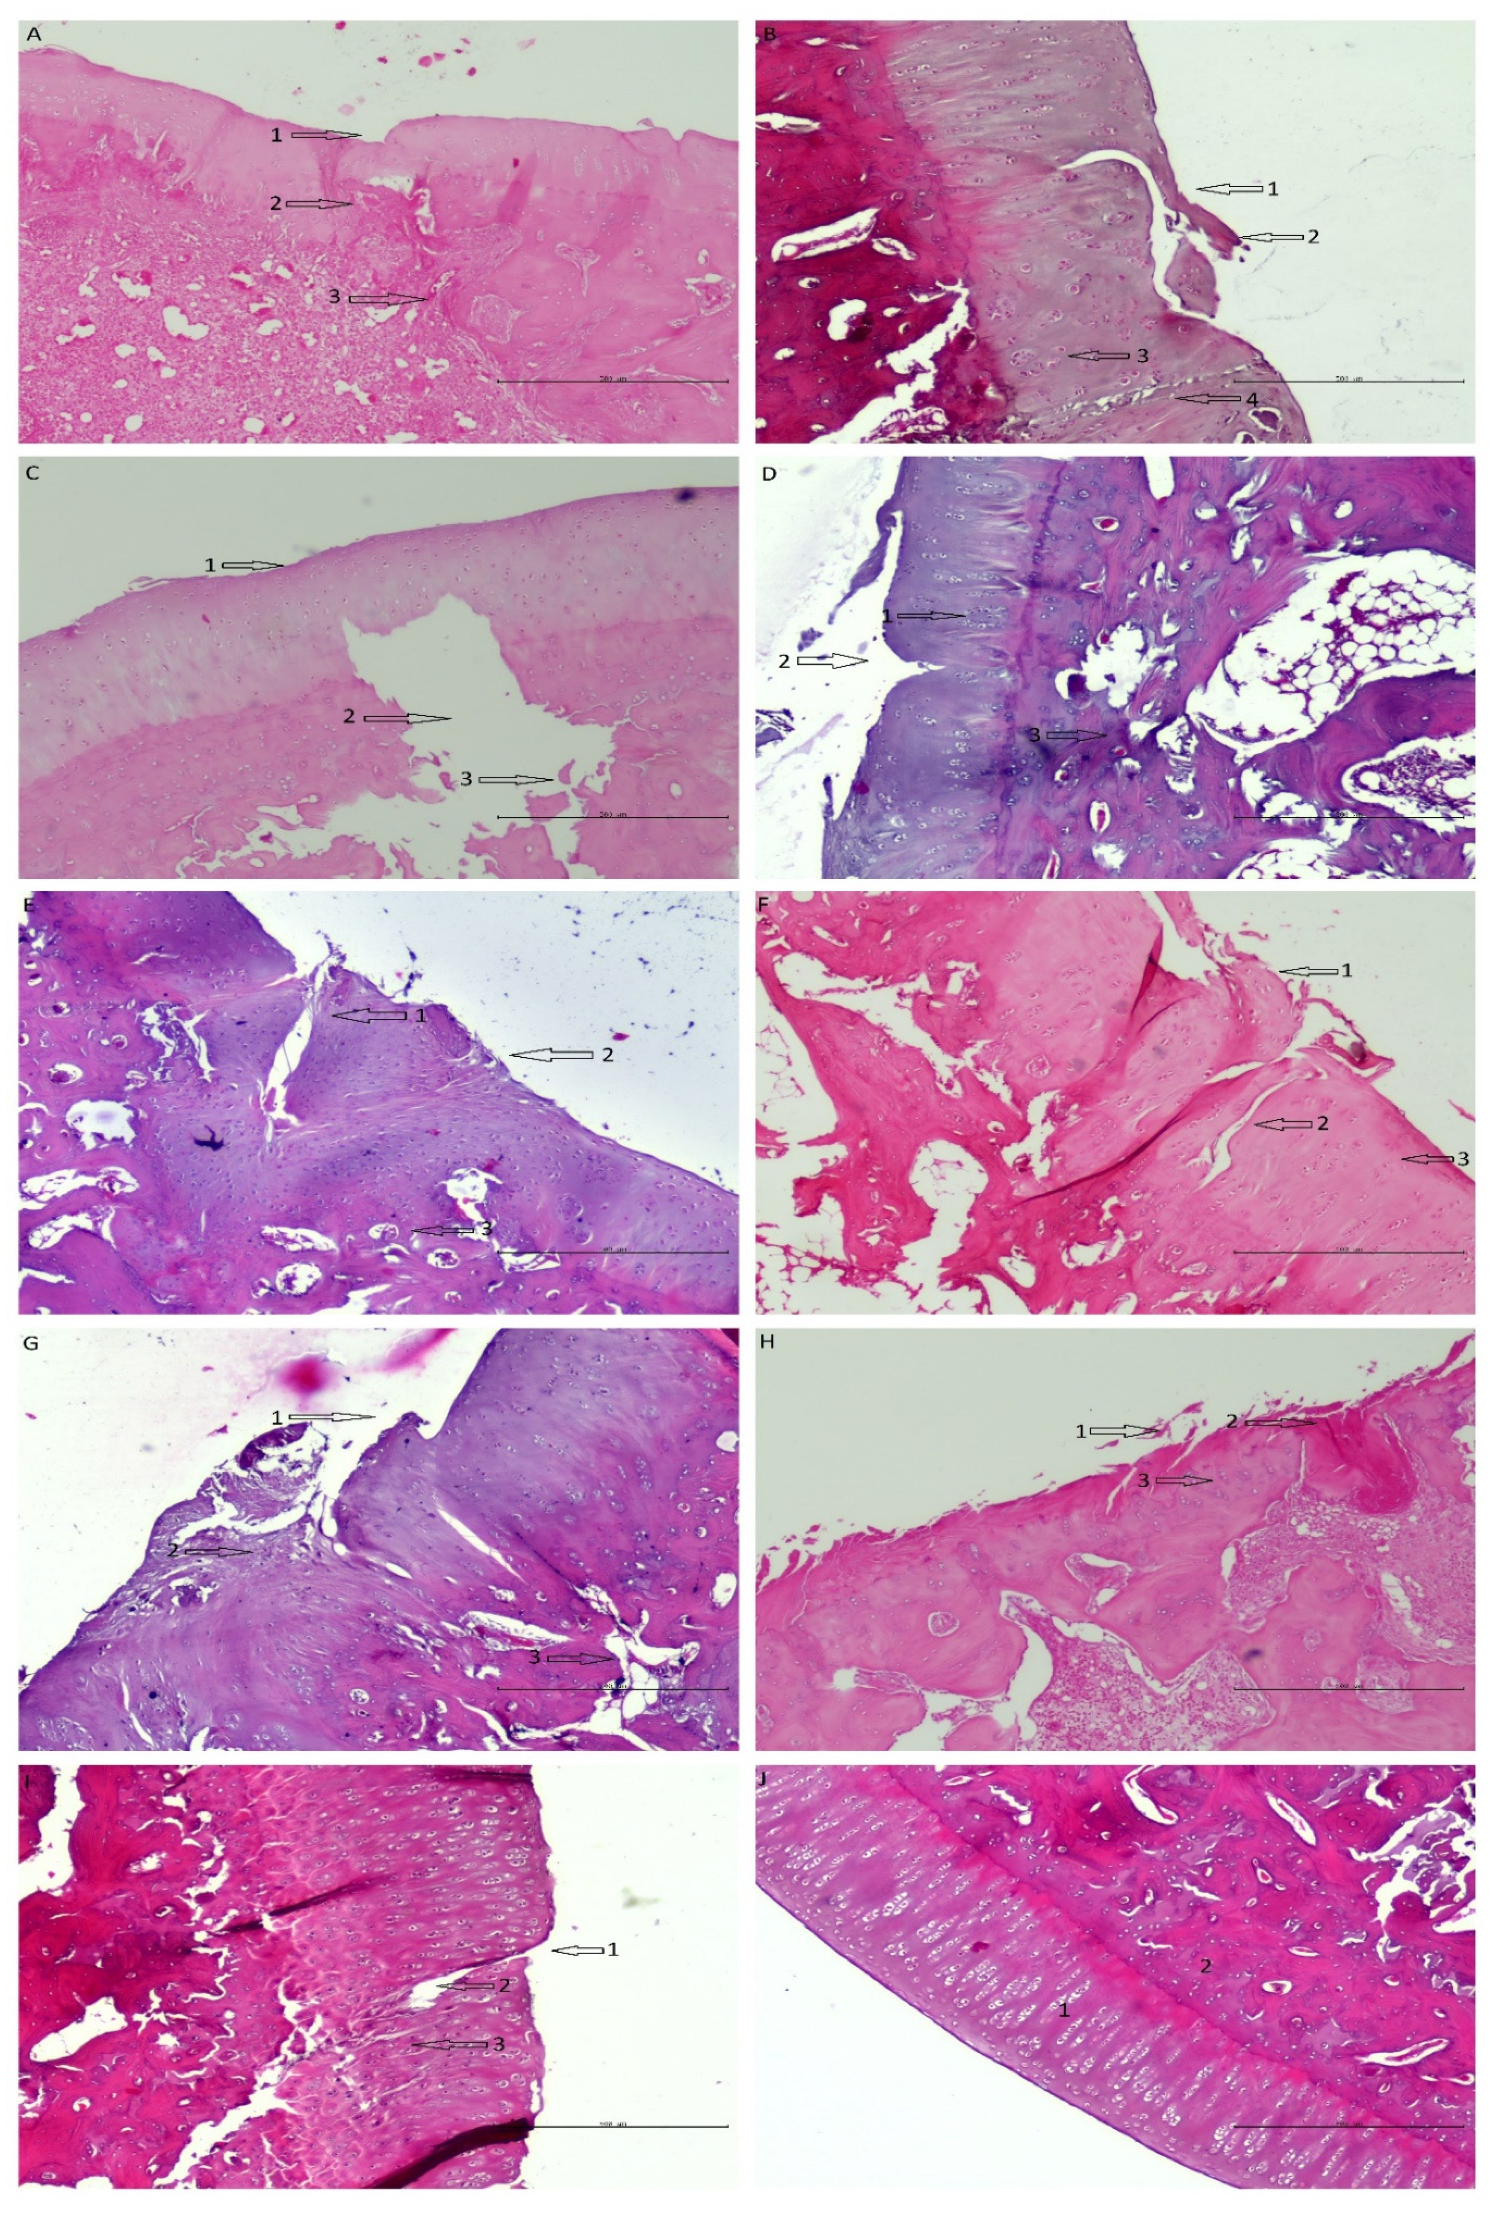

2.2.5. Histopathology

- Paraffin sections were stained by the routine hematoxylin–eosin method.

- The regenerates were evaluated (ICRS microscopic scoring system) under a light microscope by two trained and blinded observers. Each observer rated 1 regenerate 3 times at weekly intervals. The final score is the average of 3 measurements [60].

3.2. Histopathology

3.2.1. Differences in Membranes Performance

3.2.2. Histologist 1

3.2.3. Histologist 2